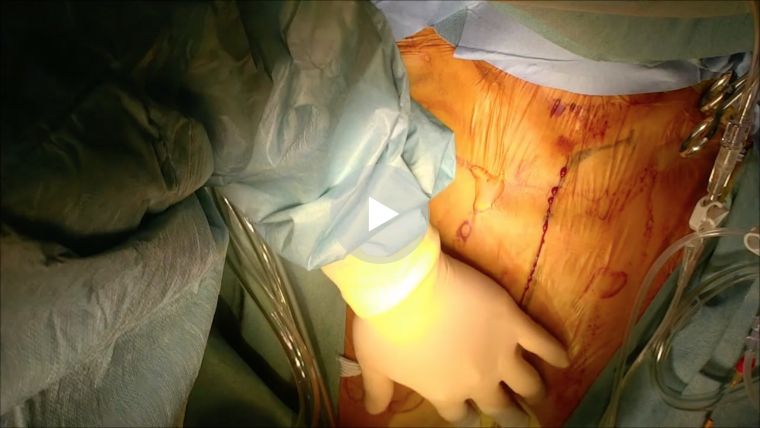

主に一箇所のバイパスを行う場合に有用な方法です。小さい傷で行う場合、内胸動脈を採取が困難となる問題があります。カメラを用いない直視法では、視野が悪い為、傷が大きくなりさらに肋骨の間を器具で大きく広げるために、疼痛や美容的な問題があります。3D内視では広い範囲の動脈を小さい傷で採取できる為、これらの問題を解決できる利点があります。ただし、内視鏡採取は豊富な経験が必要な為、全国的にも限られた施設でしか行っておりません。

吻合は傷を痛めないように組織に優しい器具を用いて行います。

この方法を基本として、複数の血管へのバイパス手術を行っています。